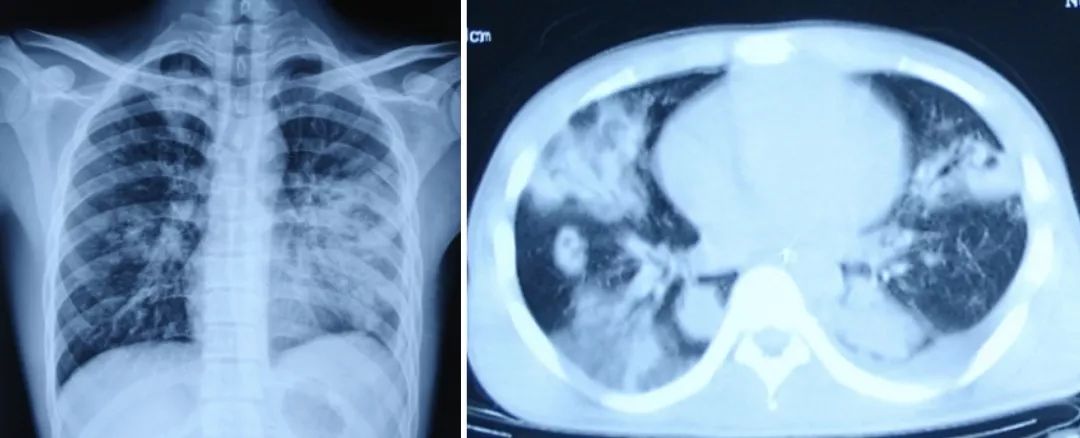

由细菌感染导致的流感患者的肺炎,称为流感病毒相关性细菌肺炎,它比单纯性流感病毒肺炎更为常见 [10]。临床表现为咳脓性痰,外周血白细胞明显增多,以中性粒细胞为主。胸部影像基础病变为浸润影和实变影(图3-4),可表现为支气管肺炎或大叶性肺炎 [11]。流感病毒相关性细菌肺炎还可分为两种类型:「细菌同时感染型」和「继发细菌感染型」[12]。前者是指当流感症状减轻后2~7天,在受损的肺或支气管上继发细菌感染;后者是指在流感病毒感染的同时,即有细菌感染。后者的临床表现一般比前者更为严重。

(图3、图4)